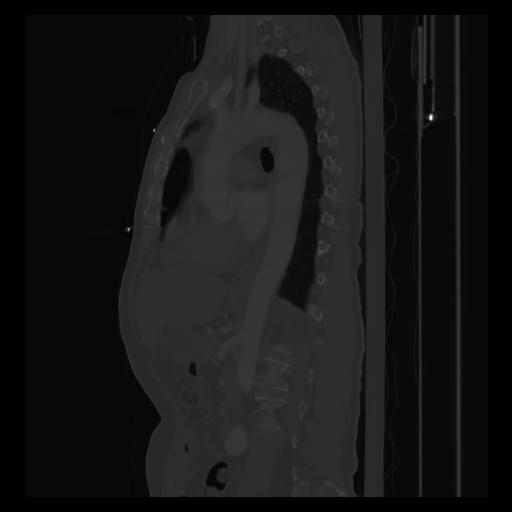

30 CUERPO,CE,Sagittal,3.000,CUERPO,Sagittal,